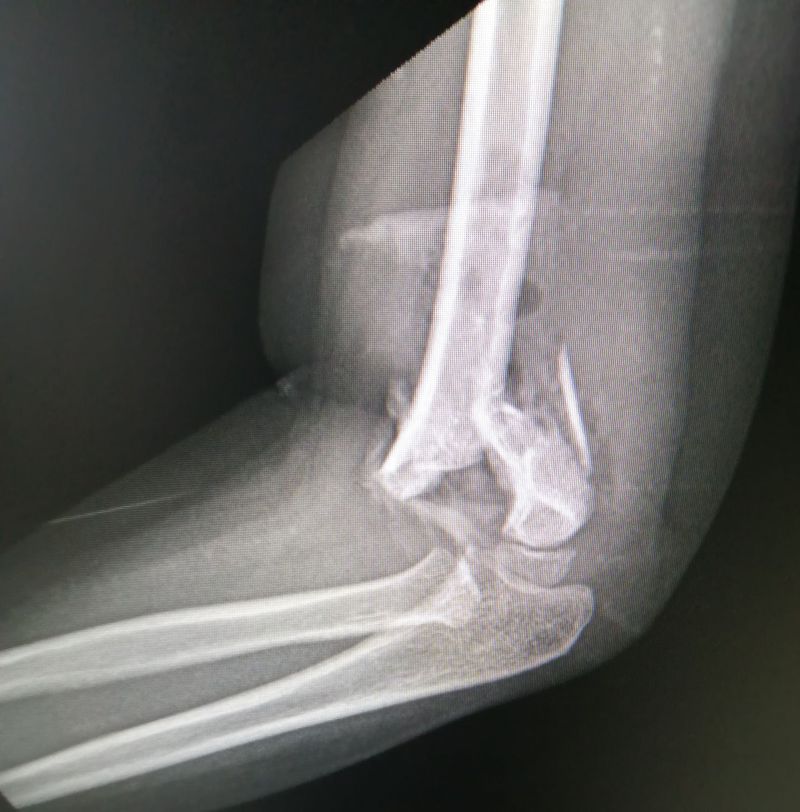

Elbow LAT View

Distal humerus fractures.

Supracondylar